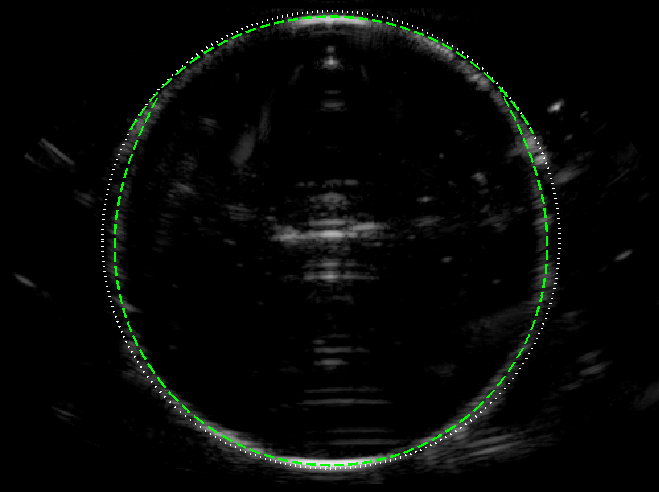

Experimental B-mode images (with curved array) of the circular test object are shown in figure 5, alongside the ray model predictions, for following 3 speed of sound scenarios.

-

(c) : Lastly, we take m s-1 (water) and m s-1 (ethanol-water mixture), giving . The ambient liquid is no longer matched to the scanner calibration, causing the near face to become slightly shifted towards the far face. Again, the overall image shape agrees well with the ray model (in this case in based on the extended theory in Appendix A).

These results validate the use of the ray model in predicting the geometric distortion of the object boundary.